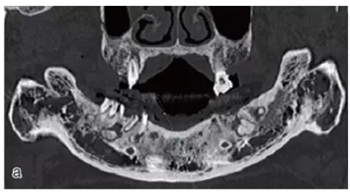

術(shù)前拍攝錐形束CT,進(jìn)行三維重建和種植方案規(guī)劃。從CT圖像中可以看出頜骨內(nèi)有骨島和殘根,為避免種植體植入骨島區(qū),考慮在兩側(cè)頦孔區(qū)種植4~5顆種植體,采用套筒冠進(jìn)行即刻修復(fù)。從重建的結(jié)果中可知前牙區(qū)牙槽嵴呈刀刃狀。種植方案為:對前牙區(qū)牙槽嵴進(jìn)行截骨修整,并在兩頦孔之間的區(qū)域內(nèi)植入5顆種植體。

圖15 種植方案的規(guī)劃:a.患者的CT圖像的截面圖,圈紅處為骨島;b.患者摘掉活動義齒后的下頜;c.患者上下頜骨的CT三維重建;d.下頜骨截骨后模擬植入5顆種植體